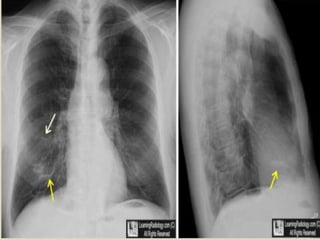

 Signs on CXR include the identification of

parallel linear densities, tram-track opacities, or

ring shadows reflecting thickened and

abnormally dilated bronchial walls. These

bronchial abnormalities form a spectrum from

subtle or barely perceptible 5-mm ring

shadows to obvious cysts. Tubular branching

opacities conforming to the expected bronchial

branching pattern may result from fluid or

mucous filling of bronchi